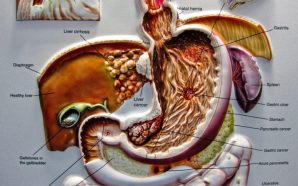

Colon cancer, or colorectal cancer, involves the growth of one or more tumors in the large intestine and rectum. As colorectal cancer is both preventable and treatable, it is important to recognize the symptoms: A change of bowel habits Blood in the stool Diarrhea, constipation, or a feeling that...

What Causes Colon Cancer? Colon cancer is the name given to cancer in the large intestine, usually resulting from the cells of the colon mutating and multiplying to form cancerous polyps on the intestine. Colon cancer is one of the most common cancers identified in both men and women...

Important Facts To Know About Colon Cancer The colon is considered as one of the most important parts of our digestive system. When the malignant tissue in Colon grows then the Colon Cancer is occurred. The digestive system is harmed by it very seriously. It is the most harmful...

Colon cancer is the development of cancer in the colon, or large intestine. It generally begins as small, noncancerous lumps, known as adenomatous polyps, that are asymptomatic and can take some time to turn into full-blown cancerous cells. This is largely the reason yearly colon cancer screenings are recommended—the sooner...

How is Colon Cancer Treated? Treatment for colon cancer depends upon the stage of the cancer when discovered. Initial screenings such as colonoscopies and sigmoidoscopies can detect pre-cancerous tumors in the colon. These tumors can be removed and tested for cancer. These preventative screenings are extremely important in preventing...